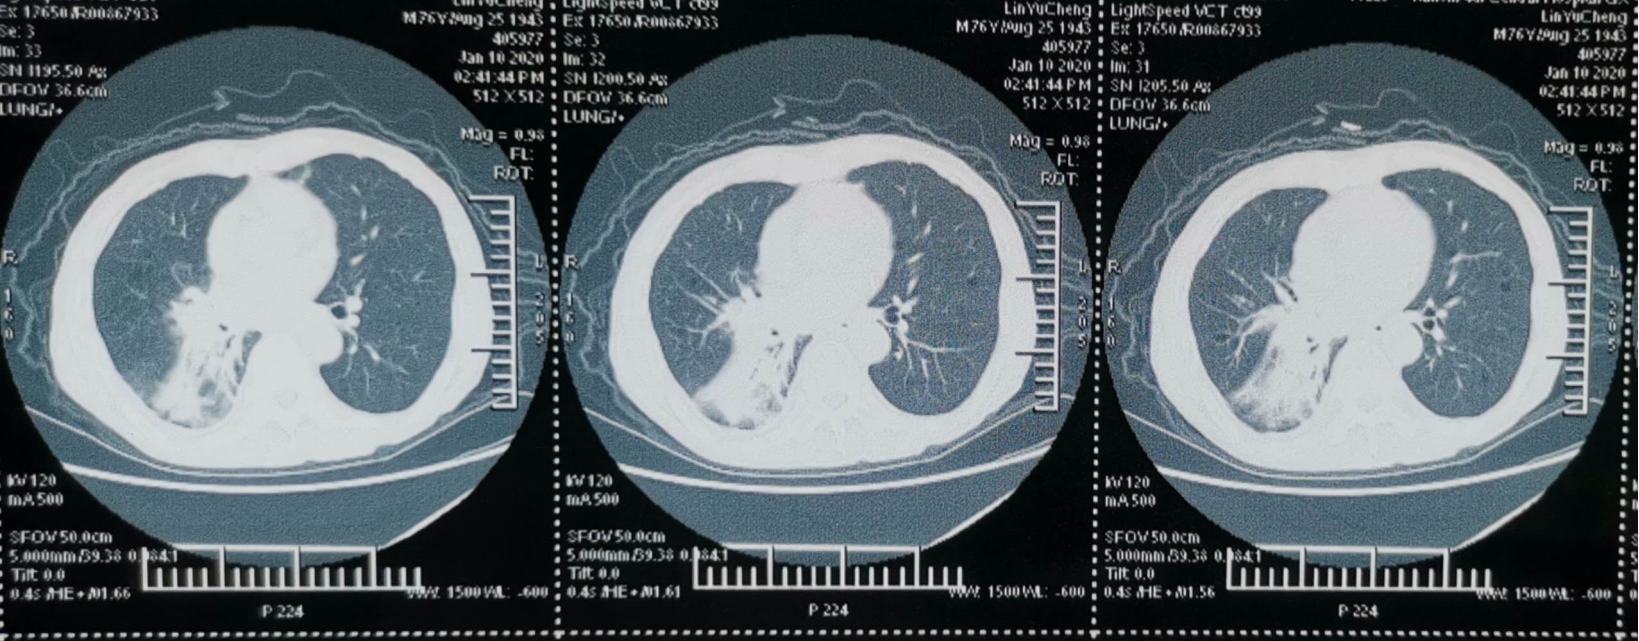

2020-01-10 胸部CT(图1):符合右肺癌伴肺门及纵隔淋巴结转移;考虑右肺下叶基底段阻塞性炎症改变及充气不良;考虑右肺下叶背段肺不张;右肺下叶癌性淋巴管炎不除外;考虑右中叶陈旧病变可能大;两侧肺气肿、多发肺气囊;右下叶基底段支气管痰栓;右侧胸膜病变,转移不除外;右侧胸腔积液;肝脏囊肿;考虑双侧肾上腺转移;腰1骨转移不除外。

2020-01-13头部CT(图3):未见明显异常。

在诊断方面,患者于外院行支气管镜活检病理提示腺鳞癌,但未系统治疗。后为求进一步诊治转入我院,经完善胸部CT、全腹CT、头颅CT等影像学检查,并结合穿刺活检、免疫组化及基因检测,最终明确诊断为原发性支气管ASC,伴右肺门、纵隔淋巴结转移,以及骨、肾上腺、胸膜、左下腹软组织等多发转移。